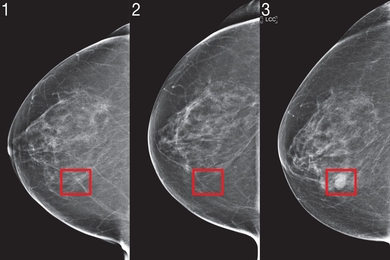

Researchers created a risk-assessment algorithm that shows consistent performance across datasets from US, Europe, and Asia.